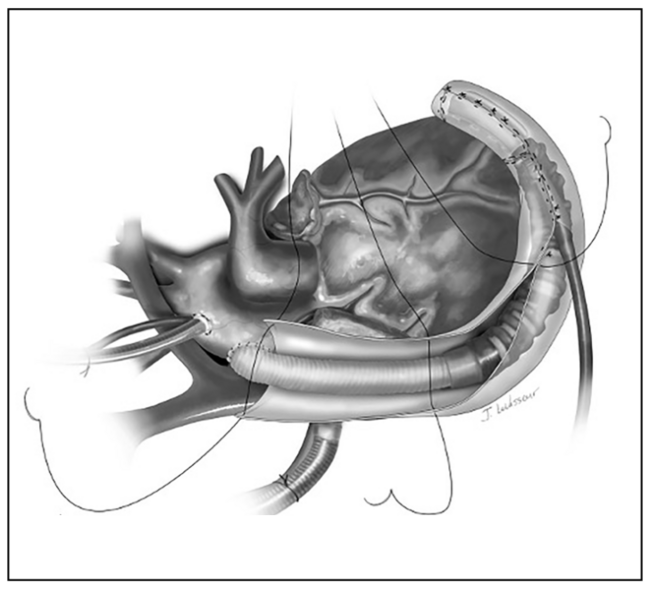

A 60-year-old female underwent a left ventricular assist device (LVAD) implant during which a 1-mm Gore-Tex sheet (Gore Medical) was used to cover the device and outflow graft to prevent future sternal re-entry injury (Figure 1). Seven years later, she developed low-flow alarms with a pattern of gradual decline in flow and power suggestive of outflow graft obstruction (Figure 2).